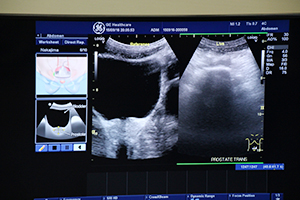

続いて,医療法人松尾クリニック理事長の松尾 汎氏が「かかりつけ医のための血管超音波手技の実際」と題して講演とハンズオンを行った。松尾氏は血管エコーの歴史を紹介した上で,静脈血栓や腹部大動脈瘤など,各部位の血管疾患を超音波検査で評価するポイントを概説。血管エコーは,最適な画像を描出し(見る),観察・計測し(観る),診断・臨床に生かす(診る)ことで,非常に有用な診断ツールとなると述べた。そして頸動脈エコーを取り上げ,スキャンや計測のためのプローブの操作法などのテクニックを説明した上で,生活習慣病を克服するために開業医に求められる内中膜複合体厚(IMT)やプラークの評価における,観察ポイントやリスク評価について解説した。ハンズオンでは,患者の体位やプローブの操作方法,LOGIQ V5に搭載されている“ドプラ自動計測機能”などを紹介した。

松尾氏による頸動脈エコーのハンズオンセミナー |

ハンズオンセミナーでは,リアルタイム超音波画像とともにプローブを操作する手元映像もWeb配信され,視聴者にとって実践的な内容となった。 |